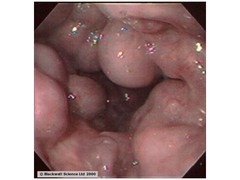

Ulcerative Colitis

- ULCER (just mucosa/submucosa) - COLON (starts in rectum and works it way up CONTINUOUSLY through colon to cecum) --> LLQ pain with BLOODY diarrhea - Microscopic: crypt abscess (neutrophils) - Gross: pseudo polyps (the part that isn't eroded appears raised) and loss of haustra (flat pipe) - Complications: toxic megaCOLON, carcinoma - Associations: p-ANCA, primary sclerosing cholangitis - Smoking PROTECTS